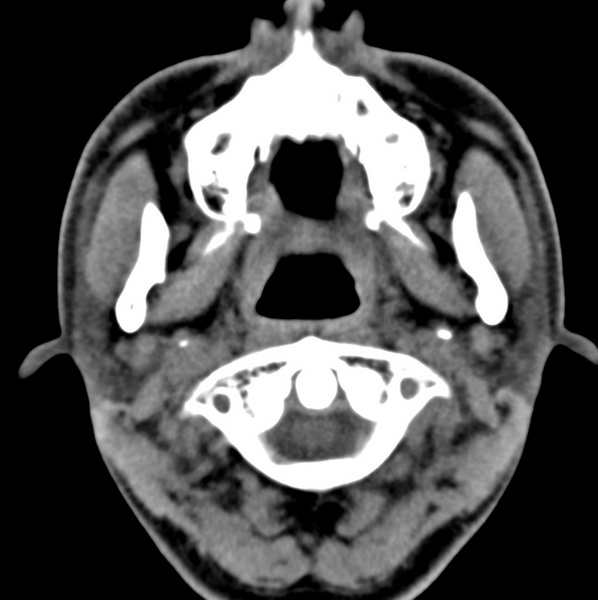

男、31、鼻咽部肿瘤放疗后请帮忙看看。

效果好,右侧破裂孔扩大,局部骨质缺损,为颅底骨质破坏。

1)鼻咽部肿瘤侵犯颅底放疗术后改变。2)左侧蝶窦炎。

咽后壁增厚,左侧咽鼓管隆突增大、咽鼓管咽口变浅,同侧咽旁间隙较窄。右侧颅底骨质破坏?为什么不在同一侧?

鼻咽部肿瘤侵犯颅底放疗术后改变.